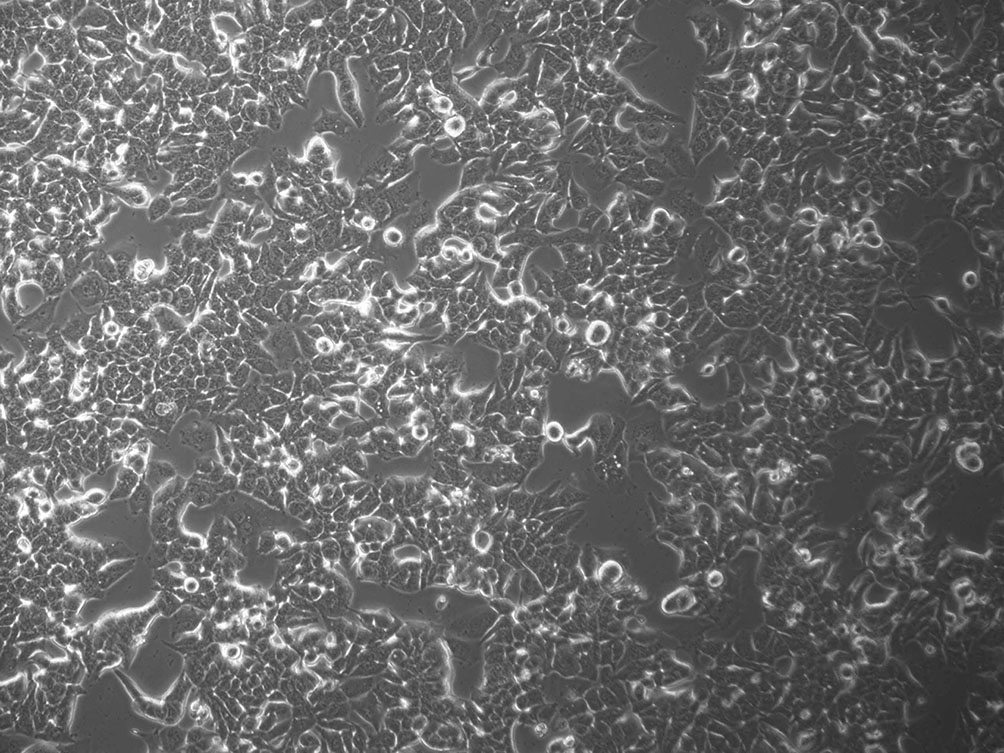

本细胞株的培养图片如下: